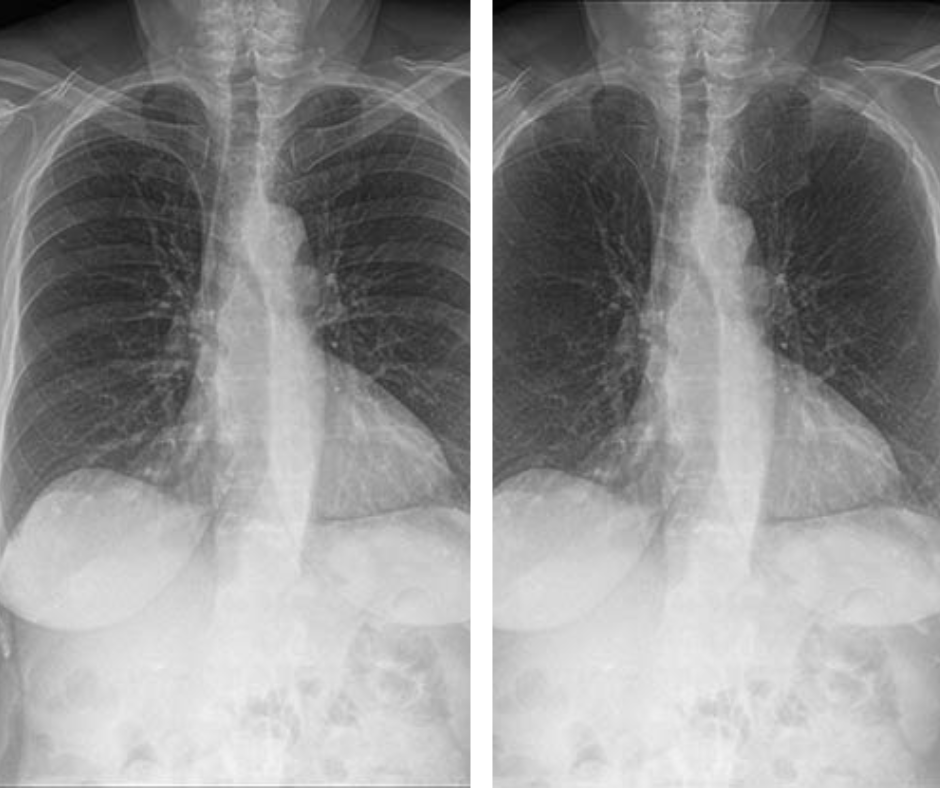

In an external validation data set for a deep learning bone-suppressed (DLBS) model, researchers found that adjunctive use of the DLBS model led to a nearly 15 percent increase in sensitivity for detecting pulmonary nodules on chest X-rays in comparison to radiologist assessment.